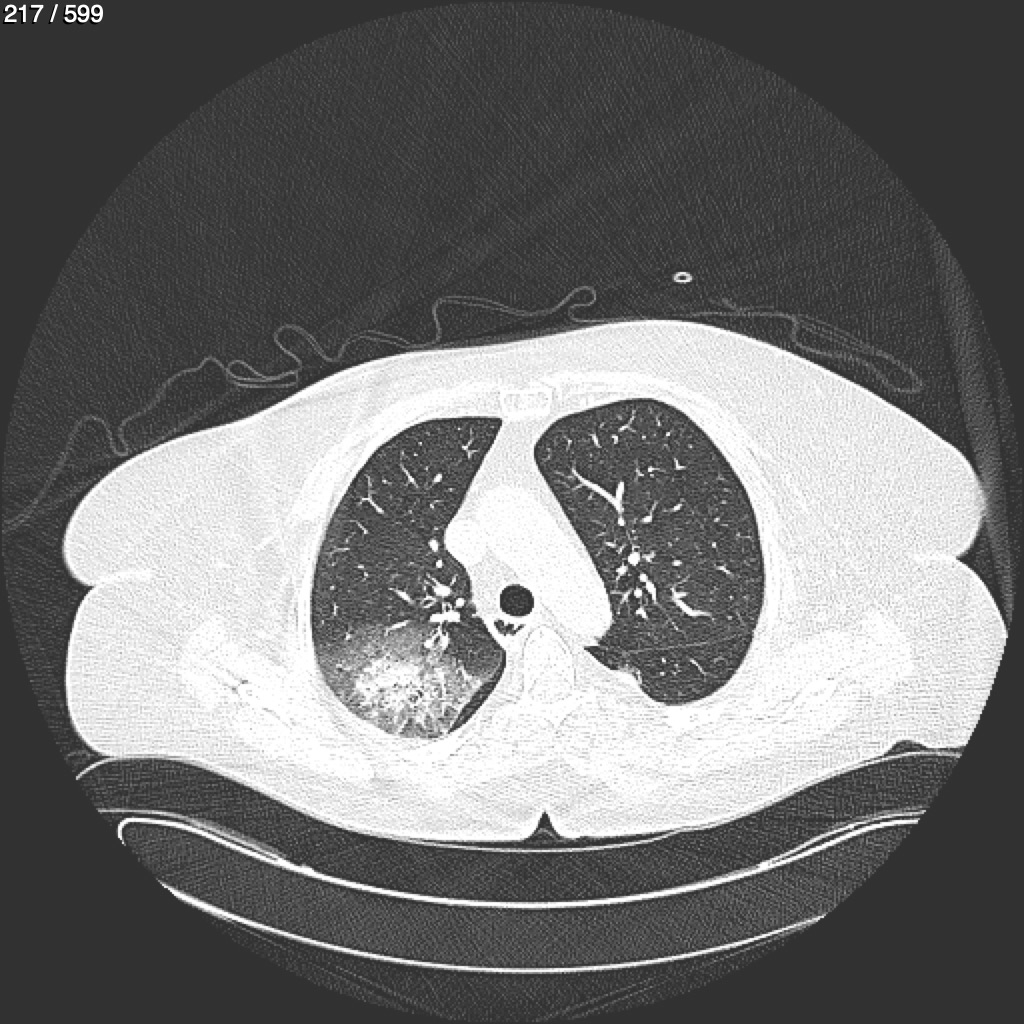

Home G​l​o​r​i​a​ ​G​l​a​d​y​s​ ​B​e​a​s​l​e​y​ ​-​ ​T​ó​r​a​x​ ​T​o​r​a​x​_​S​i​m​p​l​e​ ​(​A​d​u​l​t​o​)